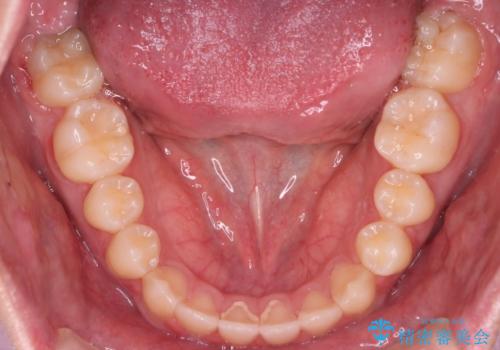

- 前歯の歯並びと噛み合わせを主訴に来院されました。

左右の噛み合わせが反対咬合であることと下顎の皮質骨が薄いため治療計画をしっかりと立てて行う必要のあるケースでした。

その点を考慮して、リンガルアーチを用いて奥歯を遠心移動し、前歯にIPR(歯と歯の間を削る処置)を行うことでスペースを作って歯並びを整えていく計画を立てました。